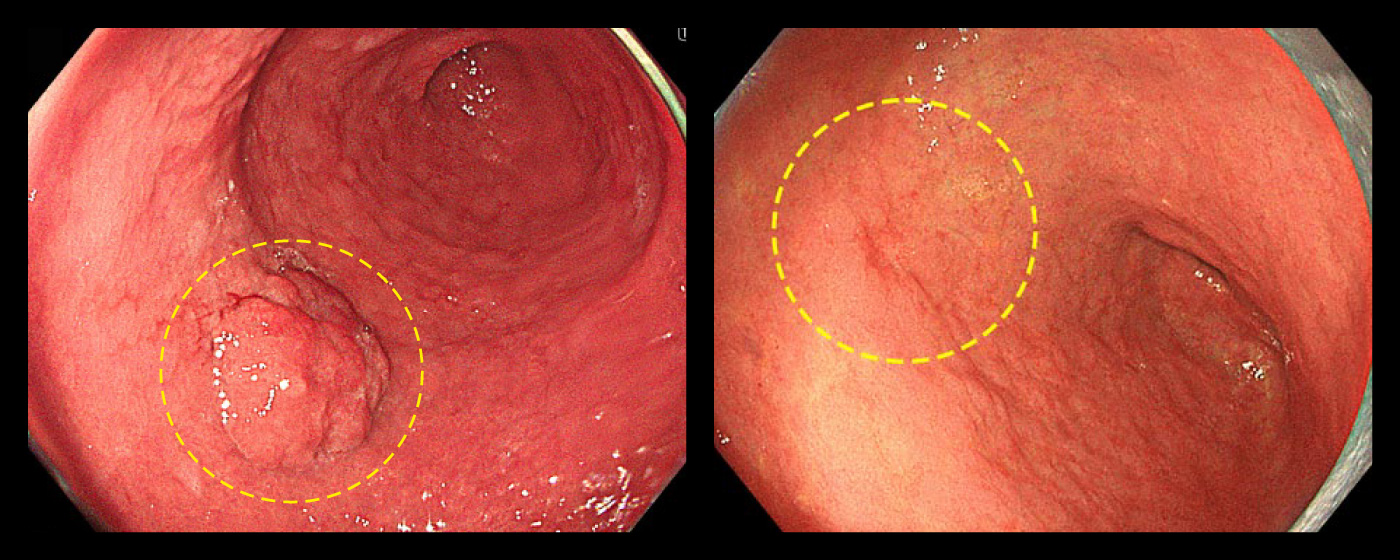

ピロリ菌感染を主因として発生した胃潰瘍

左:ピロリ菌感染を主因として発生した胃潰瘍/

右:ピロリ菌感染を主因として発生した十二指腸潰瘍

ピロリ菌感染を主因として発生した胃がん